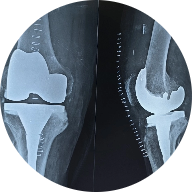

Knee replacement surgery, also known as knee arthroplasty, is a common procedure to relieve pain and restore ..... Read More

Dr. Praneeth Reddy performed knee replacement surgery on my mom. He is extremely friendly, patient, and kind. He took the time to clarify all our doubts, explained the need for the surgery, its pros and cons, as well as pre- and post-surgery precautions. He also provided detailed information about the materials used in the surgery. Dr. Praneeth is always available to address any concerns. He is truly the best doctor I have ever met.

Knee replacement surgery, also known as total knee arthroplasty (TKA), is a common procedure performed to alleviate chronic knee pain and...